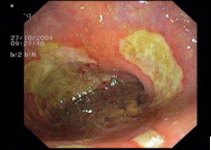

Endoscopic images:

imagen1

Endoscopic image of a flat polyp in the colon, before (left) and after resection.